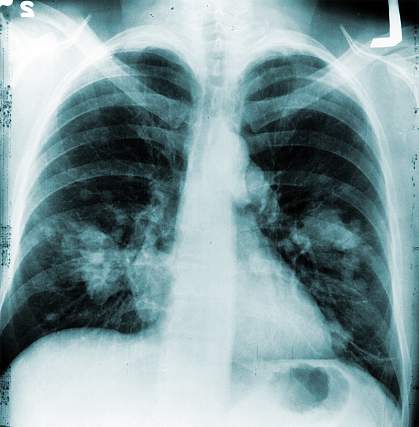

Annual Chest X-rays Don’t Cut Lung Cancer Deaths

A large multi-center study reports that annual chest X-ray screening offers no benefits over standard medical care in reducing deaths from lung cancer. The finding confirms the results of earlier, smaller studies, which suggested that chest X-rays aren't an effective tool for reducing lung cancer deaths.

After up to 13 years of follow-up, the researchers found no significant reduction in lung cancer deaths among those who received annual chest X-rays (1,213 deaths) compared to the usual care group (1,230 deaths). The types of lung cancer detected in both groups were generally similar.